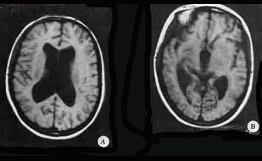

问题 如图所示,可以得出()

选项 A.颅内血肿 B.侧脑室及第三脑室扩大 C.中脑导水管狭窄 D.导水管轻度扩张,四脑室轻度增大 E.以上均不对

答案 B